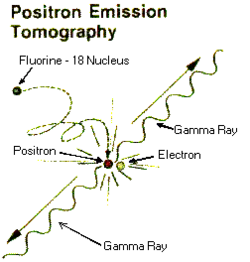

Positron emission tomography (PET) is an imaging technique, using radioisotopes also most often produced with a cyclotron.[9] They are injected into the patient, accumulating in the target tissue, and decays through positron emission. The positron annihilates with an electron nearby which results in the emission to two gamma rays (photons) in opposite directions. A PET camera detects these rays and can determine quantitative information about the target tissue.[10]